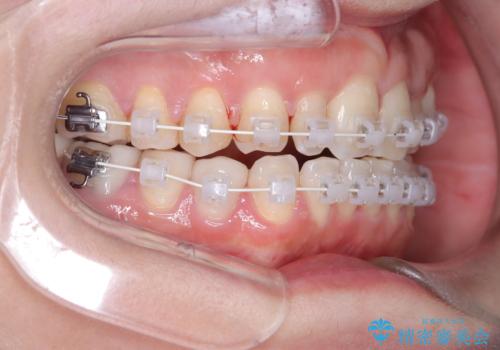

- 40代の患者様で、左上の**八重歯(犬歯の突出)**をずっと気にされていたものの、年齢的な不安から治療を迷われていたとのことでした。精密な検査の結果、左上の歯列に八重歯を収めるための十分なスペースがないことが判明。

40代は歯周組織の健康維持も重要なため、無理な拡大を避け、左上4番(第一小臼歯)を抜歯して確実にスペースを確保する計画を立てました。装置には、歯を三次元的にしっかりとコントロールでき、確実な移動が見込めるワイヤー矯正を選択。八重歯を正しい位置へ誘導し、健康的で美しい口元を目指しました。

まず、計画通り左上4番を抜歯し、そのスペースを利用して八重歯を徐々に正しい位置へと移動させました。ワイヤー矯正特有の「歯を細かく、確実に動かす力」を最大限に活用し、歯根の向きまで丁寧に調整。